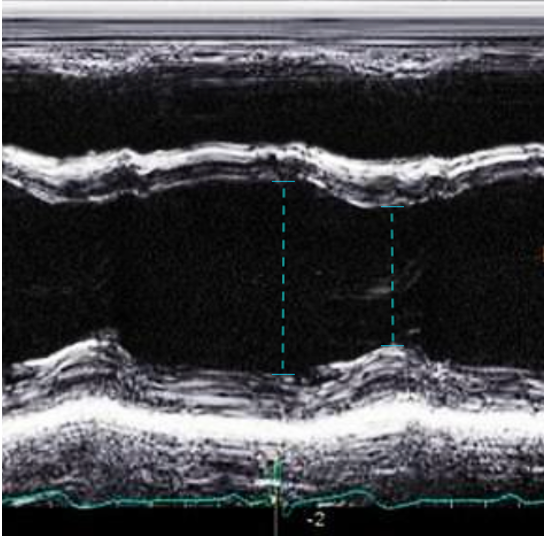

In the PLAX view, M-mode is commonly used to assess LVfx by placing the cursor perpendicular to the IVS and posterior wall at the level of the MV tips. This provides a time-motion trace of LV wall motion and cavity size throughout the cardiac cycle, with distance displayed on the y-axis and time on the x-axis allowing evaluation of systolic function.

You’ll see a wave-like motion tracing of the MV leaflets movement across the cardiac cycle. In early diastole, the AMVL rapidly opens toward the IVS, creating the tall E-wave, followed by a smaller A-wave from atrial contraction (figure 7,8).

Figure 7. M-mode

Figure 8. Zoomed-in view of the PLAX M-mode tracing at the level of the mitral valve tips.

End Point Septal Separation

The EPSS is a measure of AMVL motion and is used as a way to semi-quantify LVfx. It refers to the minimal distance between the peak of the E-wave and the IVS at the same X-axis time point (figure 8).